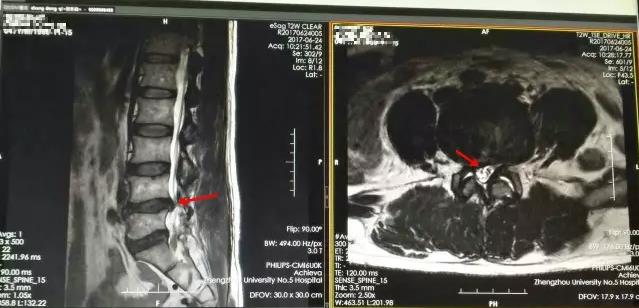

张长江教授详细查看过老刘的基本情况后判定是“腰椎间盘突出症急性发作,合并马尾综合征”,需要紧急手术治疗。一边给科里值班医生打电话准备病床,一边搀扶着行走困难的老刘走医院“绿色通道”进行影像检查,检查的结果也和张长江教授的判定不谋而合。但病是查清楚了,可是老刘怎么也高兴不起来,因为无力承担高昂的医疗费用他只能和以前一样选择放弃!

红色箭头指示为老刘20年前行开放式手术留下的刀口,蓝色箭头指示本次微创手术留下的刀口。